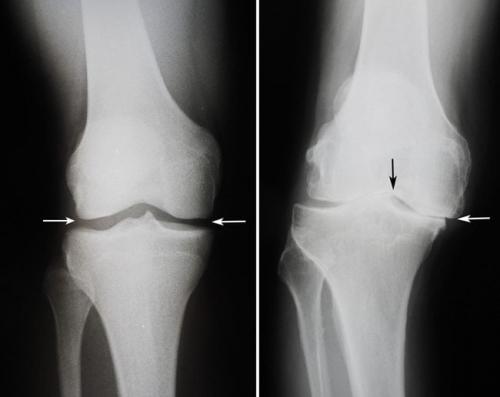

Коленный сустав. Какие бывают болезни коленного сустава: список самых распространенных

частые патологии опорно-двигательного аппарата. Около 15% пациентов ортопедо-травматологических стационаров попадают туда именно из-за проблем с коленями. Давайте посмотрим, какие бывают болезни коленного сустава.

При отсутствии лечения некоторые травмы и заболевания колена могут приводить к снижению трудоспособности и даже инвалидности. Если вас беспокоят боли,или другие неприятные симптомы – немедленно идите к врачу! Своевременная медицинская помощь поможет вам избежать тяжелых последствий.

Классификация заболеваний

В зависимости от причин возникновения все болезни коленных суставов можно разделить на несколько больших групп. Для каждой из них характерны свой механизм развития и симптоматика.

Виды заболеваний коленных суставов:

- воспалительные. Характеризуются развитием инфекционного или асептического воспаления различных структур коленного сустава. Могут возникать в любом возрасте. Причины патологиизанесение инфекции в сустав или наличие воспалительного процесса в организме.может быть как острым, так и хроническим. Воспалительные процессы также могут развиваться на фоне длительного течения;

- дегенеративно-дистрофические. Чаще встречаются у пожилых людей и лиц, которые постоянно выполняют тяжелую физическую работу. Дегенеративные процессыэто следствие старения организма, которое сопровождается замедлением метаболизма и кровообращения в суставах. Под действием провоцирующих факторов (физические нагрузки, нехватка кальция, обменные нарушения) суставные хрящи начинают разрушаться, что приводит к развитию патологии. Дегенеративно-дистрофические заболевания имеют хроническое, медленно прогрессирующее течение;

- травматические . Возникают сразу после травмы или позже, в более отдаленном периоде. Причиной может быть падение,, удар по колену или сдавление ноги тяжелым предметом. Травматические заболевания могут приводить к нарушению функционирования коленных суставов, трудностям при ходьбе и даже инвалидности. Их своевременное лечение помогает избежать нежелательных последствий;

- опухолевые . Новообразования в области колена могут быть доброкачественными и злокачественными. К первым относят остеому и, которые хорошо поддаются лечению. Ко вторым относятся множественная миелома, хондросаркома, остеогенная саркома. Как и любые злокачественных опухоли лечить их сложно. Развиваются они редко.